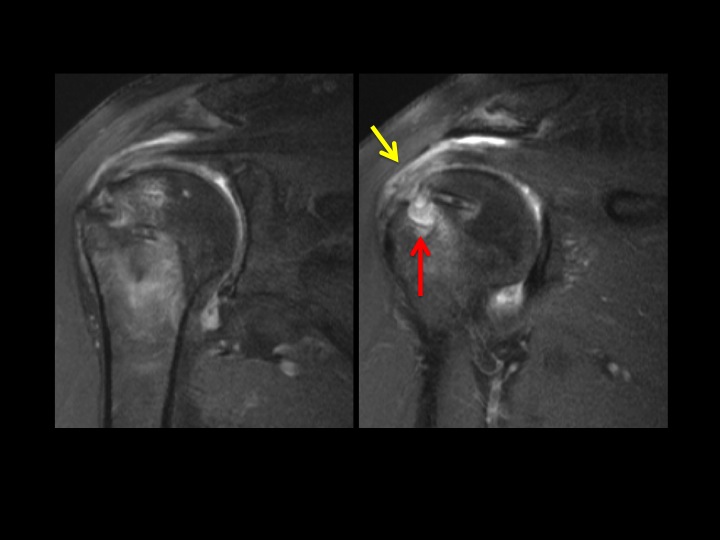

67 yr old female 1 year post RCR with shoulder pain + instability

This is always a source of confusion. There are 4 bioabsorbable anchors: 3 entering anterior to posterior at the supraspinatus insertion, 1 related to biceps tenodesis. There is a wide zone of Dark T1/Bright T2 signal with bone resorption surrounding the cuff fixations screw, but not the biceps tenodesis screw (red arrows). The supraspinatus tendon is thick and frayed, but intact. There is partial tearing of the infraspinatus and a small intrasubstance tear at the subscap insertion (yellow arrows). To what extent is the lysis surrounding these screws abnormal (there is some normal degree of lysis as the screws resorb, extrapolating from tunnel widening with ACL graft fixation). Would you report this? What would you say?